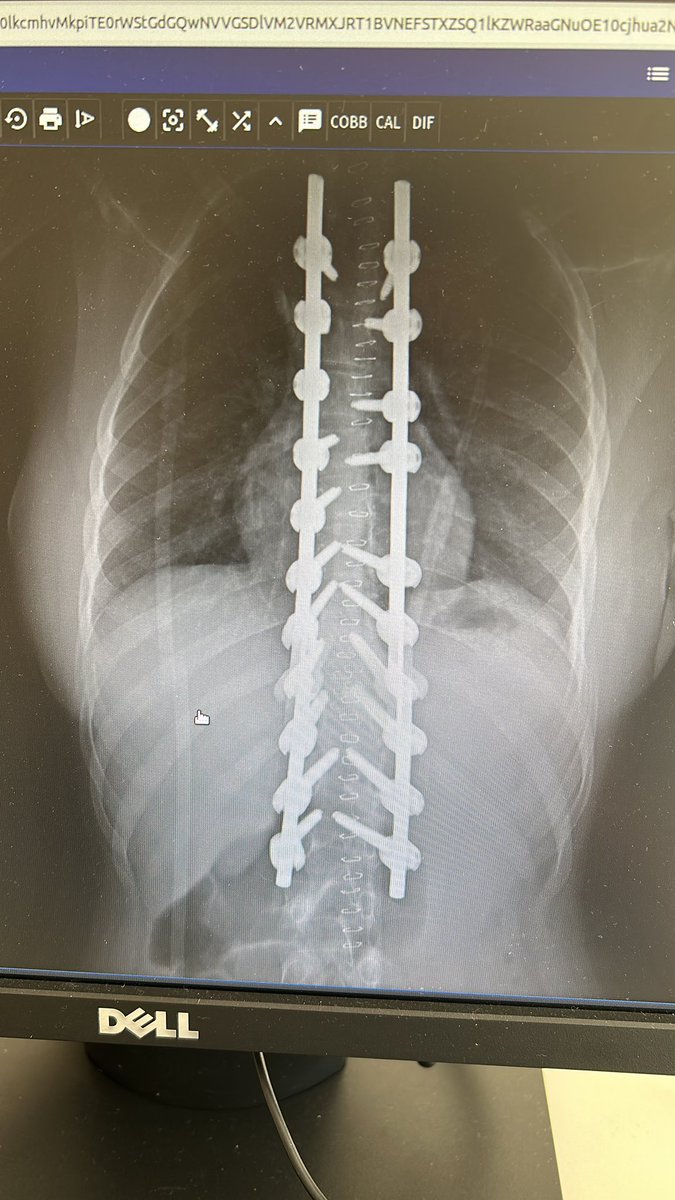

47 years old male patient, neglected (3 mounths) multilevel thoracolumbar junction spine fracture (L1, T12 and endplate of T11). there is monosegmental pure osseous failure of the posterior tension band in T12. this also called "Chance" fractures. #spinesurgery #spine